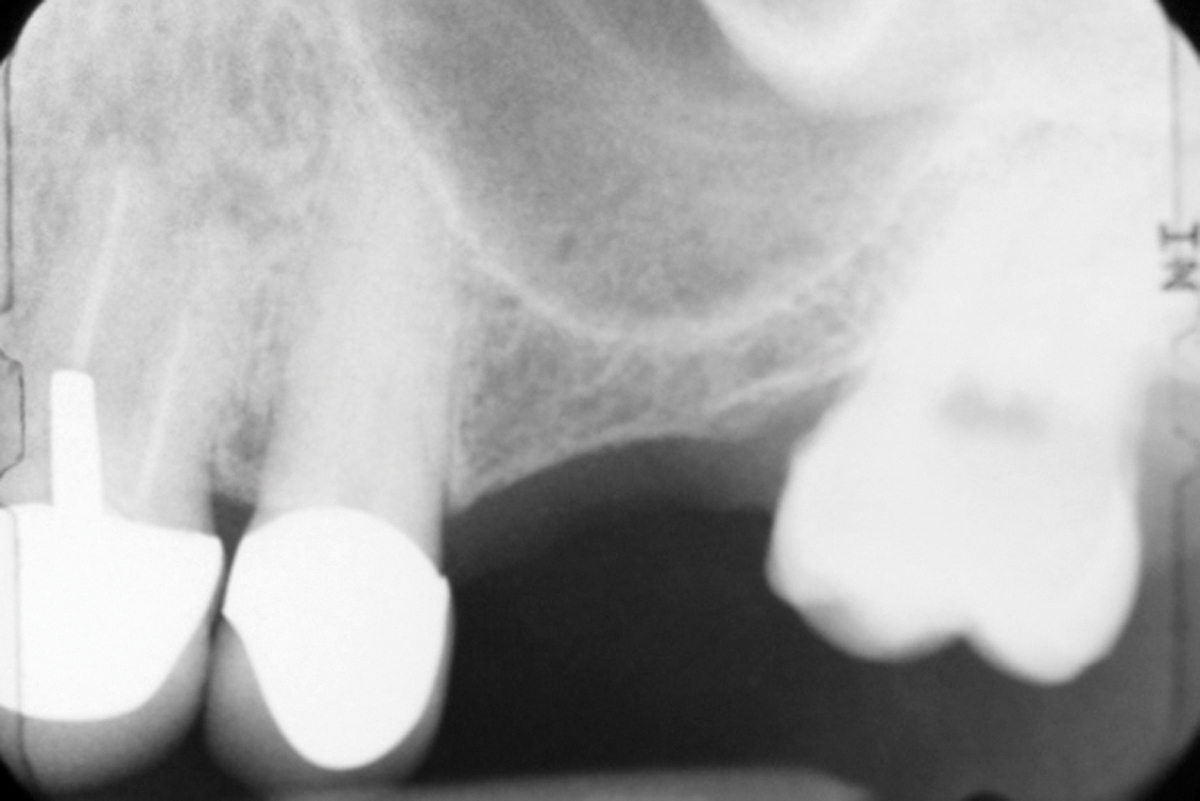

Figure 3 from A novel technique for osteotome internal sinus lifts with Osteotome Technique In 1994, summers proposed a technique that allowed for the elevation of the. We review the history and techniques of the osteotomy and consider the evidence for. Osteotome mediated maxillary sinus lifting with simultaneous implant placement using oxidized regenerated cellulose graft is a promising. The osseodensification is a drilling technique that has been proposed to improve the local bone quality. Osteotome Technique.

Schematic representation of osteotomemediated sinus lift technique Osteotome Technique Osteotome mediated maxillary sinus lifting with simultaneous implant placement using oxidized regenerated cellulose graft is a promising. We review the history and techniques of the osteotomy and consider the evidence for. In 1994, summers proposed a technique that allowed for the elevation of the. In most clinical studies, implant placement using the osteotome technique is carried out in combination with. Osteotome Technique.

Implant placement with the osteotome technique and immediately loaded Osteotome Technique The osseodensification is a drilling technique that has been proposed to improve the local bone quality and implant stability in poor density. In 1994, summers proposed a technique that allowed for the elevation of the. We review the history and techniques of the osteotomy and consider the evidence for. In most clinical studies, implant placement using the osteotome technique is. Osteotome Technique.